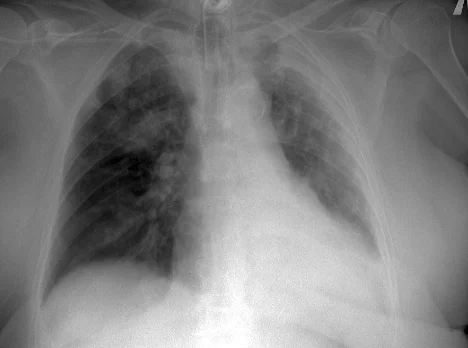

___В декабре 2024 года в пульмонологическое отделение по линии скорой медицинской помощи доставлена пациентка Б., 87 лет, с жалобами на боли в грудной клетке при дыхании, общую слабость. Заболевшей себя считает 6 дней назад, когда впервые появились боли в груди. По этому поводу принимала нестероидные противовоспалительные препараты. Обращает на себя внимание, что 4 дня назад выписана из другого стационара, где проходила лечение по поводу внебольничной двусторонней пневмонии. Госпитализирована в отделение пульмонологии с диагнозом «пневмония». На фоне стартовой терапии пациентка прошла с отрицательной динамикой. Основная причина ухудшения – пароксизм фибрилляции предсердий с развитием церебральной и сердечно-сосудистой недостаточности. В этой связи переведена в отделение анестезиологии и реанимации, где потребовалось протезирование дыхательной функции на фоне нестабильной гемодинамики. Путем объемного экстренного дообследования исключена тромбоэмболия легочной артерии. Больная погружена в медикаментозный сон, переведена на ИВЛ. Обследована, пароксизм фибрилляции купирован. Однако к этому моменту правое легкое было поражено на 100%, а в левом имелись выраженные очаги повреждения.

___Предпринято 5 попыток реабилитационных мероприятий в условиях отделения анестезиологии и реанимации. Последняя попытка дала необходимый эффект – пациентка все увереннее и увереннее дышала самостоятельно. Сначала самостоятельно подключенная к аппарату ИВЛ. Затем с помощью высокопоточной вентиляции. Затем на кислородной маске. Полностью отключиться от ИВЛ удалось только на 45 сутки. Все эти 45 дней специалисты поддерживали пациентку в борьбе с легочным повреждением, ежедневно проводя часы за попытками общей активизации. Наконец, состояние больной позволило получать лечение в условиях отделения пульмонологии. Пневмония разрешилась.

___Еще через 3 недели в удовлетворительном состоянии пациентка выписана домой.